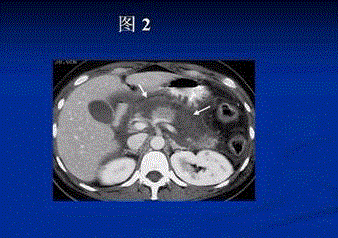

问题  患者女,66岁,上腹部疼痛、呕吐,呕吐物为胃内容物,发热、呼吸困难10 h急诊入院,发病前曾进食油腻食物。入院查 T 38.6 ℃,P 130次/min,R 32次/min, Bp 12/7 kPa(90.0/52.5 mmHg)。 此时诊断考虑的疾病可能是(提示 血WBC 24×10/L,N 0.95,Hb 120 g/L,PLT 90×10/L,血淀粉酶650 U(Somogyi法),急诊CT检查如图1和图2所示,腹部X线平片见肠腔大量积气,左上腹膈下见一单个较大液气平,无肠形,无膈下游离气体。)

选项 A、急性化脓性胆管炎 B、急性胰腺炎 C、胆道蛔虫症 D、胆总管结石 E、消化性溃疡 F、急性出血坏死性小肠炎 G、机械性肠梗阻 H、急性胃肠穿孔

答案 ABD